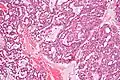

Low magnification micrograph of a polymorphous low-grade adenocarcinoma, showing the typical variation of architectural arrangement. H&E stain.

• It has a varied microscopic architectural appearance, i.e. it is polymorphous.

PLGAs consist of a monomorphous cell population that has a varied histologic morphology.

Microscopically, its histology can be confused with an adenoid cystic carcinoma and a pleomorphic adenoma.